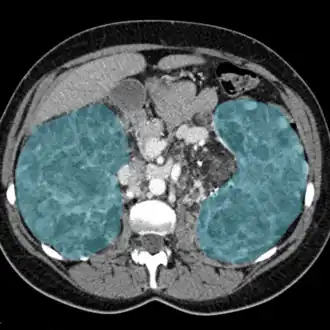

| Rins inflamados em exame de ressonância magnética (em azul). | |